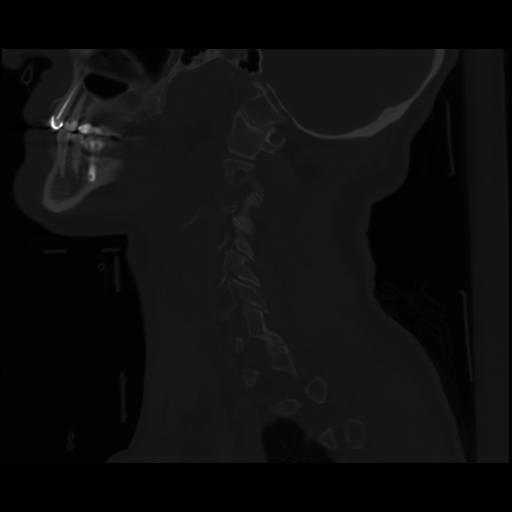

14 P.BLANDAS,,Sagittal,2.000,P.BLANDAS,Sagittal,